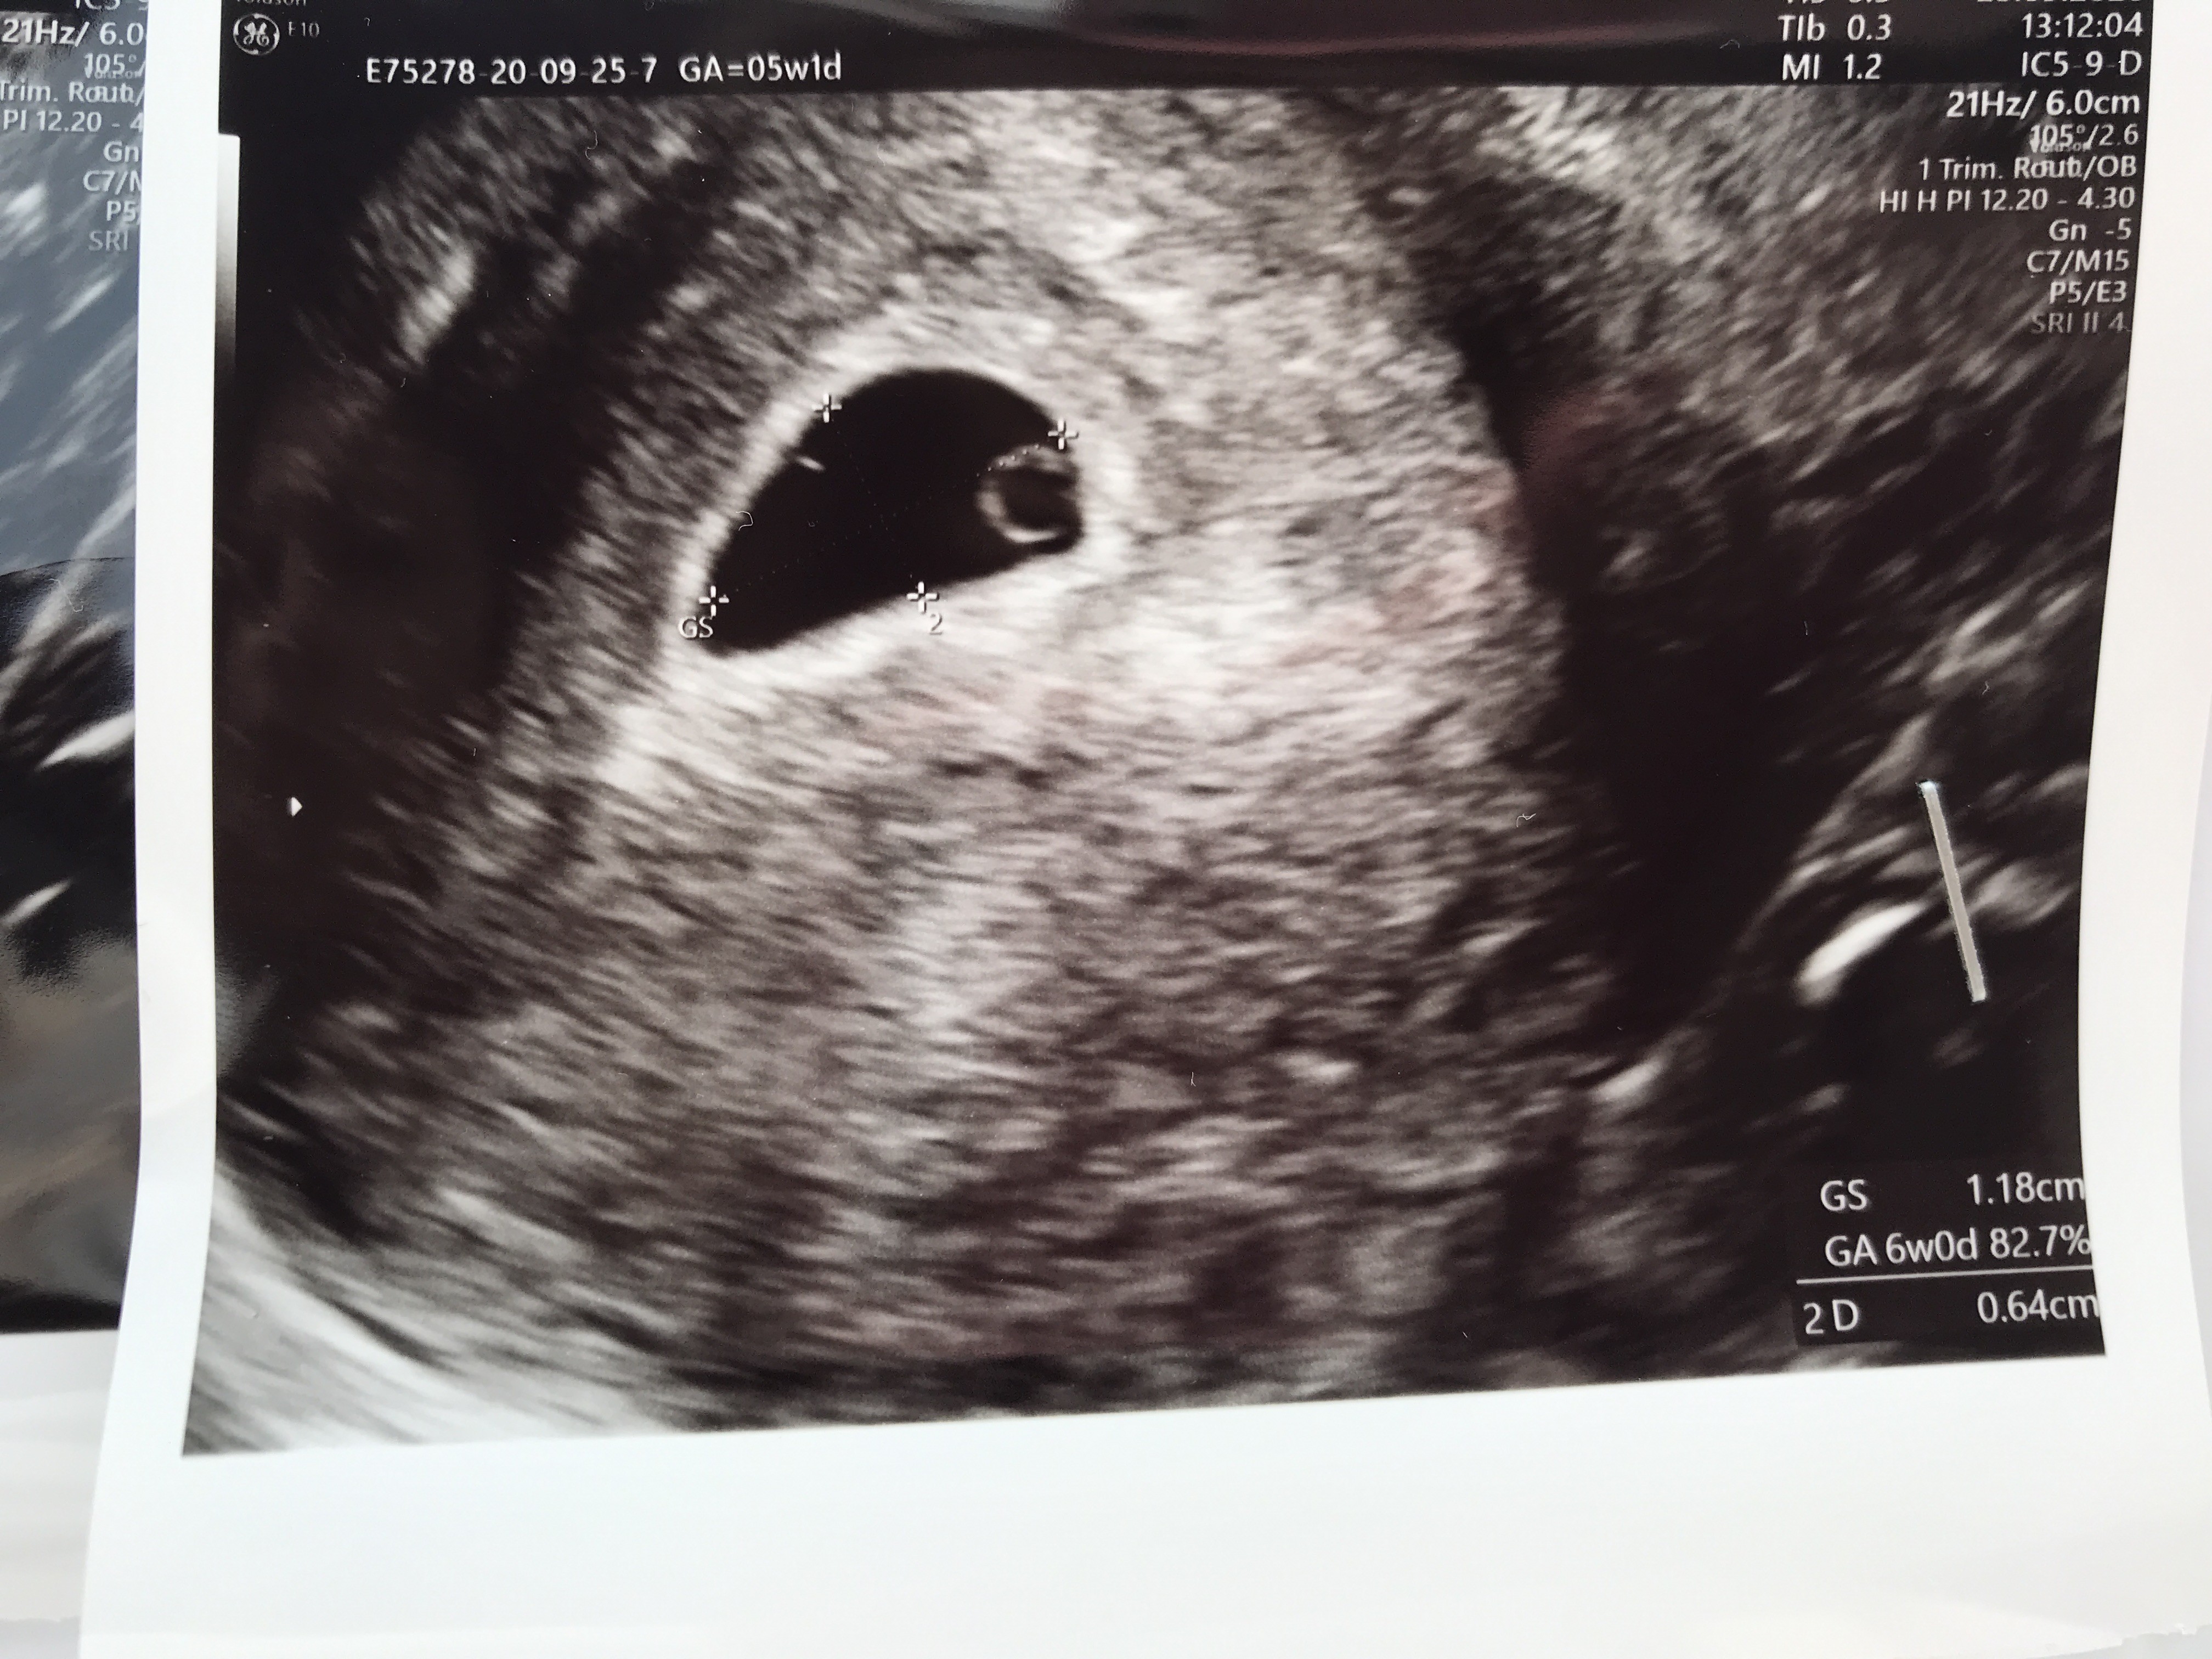

Ja po wizycie :) Ciąża wewnątrzmaciczna z widocznym pęcherzykiem zoltkowym. 5t1d wg om ale wiem ze owulacja była szybciej i z pomiaru pęcherzyka jest 6t0d. Kolejna wizyta za 2 tygodnie :)

Załączniki

• image.jpg

image.jpg

1,7 MB · Wyświetleń: 85